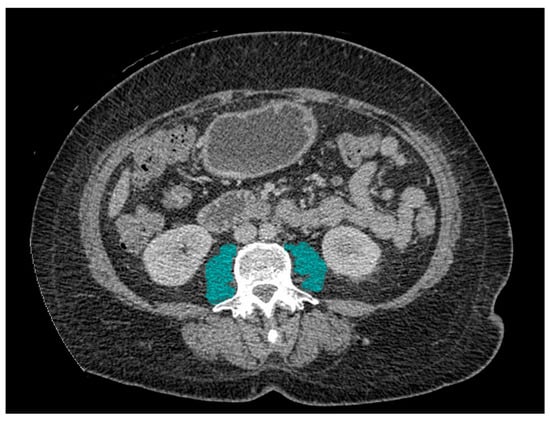

Association of Skeletal Muscle Radiodensity and Skeletal Muscle Index with Immunotherapy Response in Metastatic Non-Small Cell Lung Cancer

Muscles 2025, 4(4), 51; https://doi.org/10.3390/muscles4040051 - 5 Nov 2025

Sarcopenia and reduced skeletal muscle radiodensity have been proposed as potential biomarkers influencing the outcomes of immunotherapy in cancer patients. This retrospective study aimed to evaluate the prognostic significance of skeletal muscle index (SMI) and skeletal muscle radiodensity (SMD), assessed by means of

Sarcopenia and reduced skeletal muscle radiodensity have been proposed as potential biomarkers influencing the outcomes of immunotherapy in cancer patients. This retrospective study aimed to evaluate the prognostic significance of skeletal muscle index (SMI) and skeletal muscle radiodensity (SMD), assessed by means of computed tomography imaging at the L3 level, in 76 male patients with metastatic non-small cell lung cancer treated with PD-1/PD-L1 inhibitors. Patients were categorized into high and low SMI/SMD groups based on body mass index-adjusted cut-off values. Clinical outcomes included treatment response, overall survival, and immune-related adverse events. While no statistically significant differences in overall survival were observed between groups stratified by SMI or SMD, patients with higher SMD demonstrated a significantly greater disease control rate (56.22 ± 8.04 vs. 48.36 ± 10.34 HU; p = 0.031). Additionally, a statistically significant interaction was observed between PD-L1 expression and SMI (p = 0.027), indicating that muscle mass may influence the prognostic value of PD-L1. Neither SMI nor SMD were associated with immune-related adverse event incidence. Multivariate analysis identified PD-L1 expression ≥ 50% as the only independent predictor of longer overall survival (Hazard Ratio = 0.29; p = 0.001). In conclusion, while neither SMI nor SMD independently predicted overall survival, SMD was associated with treatment response. Notably, SMI modified the prognostic relevance of PD-L1 expression, suggesting a potential role for muscle mass in refining immunotherapy stratification.